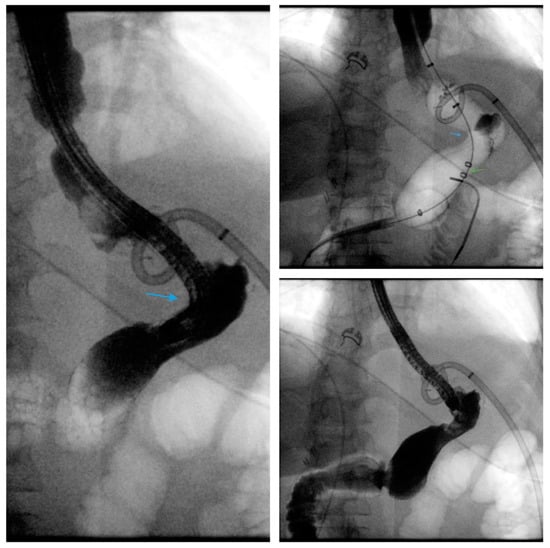

Scheme 4.

Fluoroscopic image demonstrates the placement of a 23 mm × 15 cm partially-covered esophageal self-expanding metal stent from the distal esophagus to the pylorus (arrow, top left) for the treatment of a leak in a patient following sleeve gastrectomy. Contrast injected endoscopically (arrows, top right and middle left) reveals a small, persistent sleeve leak. The endoscopic removal of the stent was subsequently attempted using a grasper (arrows, middle right and bottom left), but the stent removal was unsuccessful due to tissue ingrowth. A 23 mm × 15 cm, fully-covered, esophageal self-expanding metal stent was placed within the prior stent (arrow, bottom right) to facilitate removal after pressure necrosis of the ingrown tissue.

Scheme 7.

Gastric sleeve stenosis in the patient depicted in Scheme 5 was treated with through-the-scope balloon dilation to 20 mm as demonstrated on fluoroscopic image (arrow, left) and upper endoscopy (arrow, middle). Endoscopic contrast injection following dilation revealed improvement in the stenosis and flow of contrast (arrow, right). Note a small residual drain (green arrow, left).